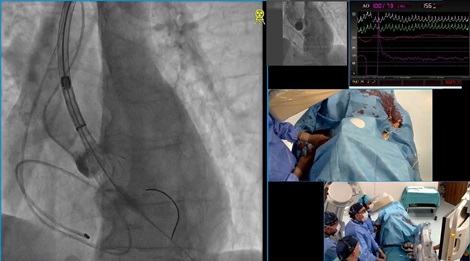

LIVE Case: Имплантация на MitraClip при пациентка с вторична високостепенна митрална инсуфициенция

Става дума за жена на 68 г. с оплаквания от задух и лесна умора, невъзможност за извършване на дейности над обичайните в ежедневието, невъзможност да лежи на ниско, с необходимост да коригира броя на възглавниците, на които спи. Тя е с богата история относно исхемичната болест на сърцето.